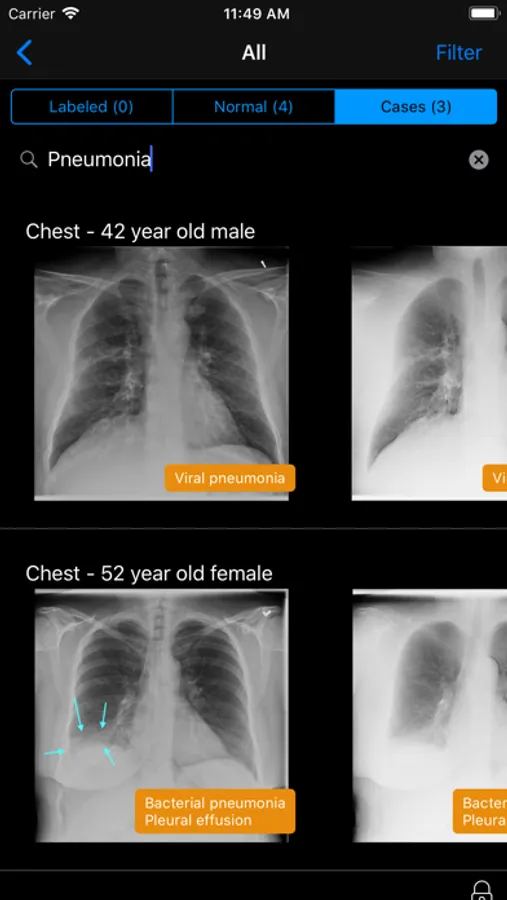

• Filter studies by patient age, gender, body region, study, diagnosis, and lateralization